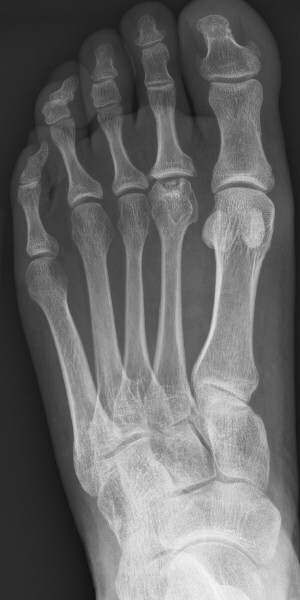

Slätröntgen som visar skleros, fragmentering och tillplattat os navikulare [1, 2] resp. huvud av metatarsalben [1].

Första bilden visar Köhler typ 1 med tillplattat os navikulare, andra bilden resttillstånd efter Köhler typ 2 i kaput metatarsale 2.